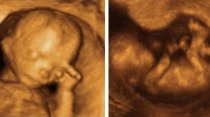

Ecografu00eda o ultrasonido de un bebu00e9 por nacer de 12 semanas. Cru00e9dito: Wikipedia (CC BY-SA 3.0

Proponen ley en Ohio para enseñar humanidad del niño por nacer en escuelas públicas

Jul 11, 2019

Recientemente se presentó en Ohio (Estados Unidos) un proyecto de ley que propone enseñar en las escuelas públicas cómo es... Leer más